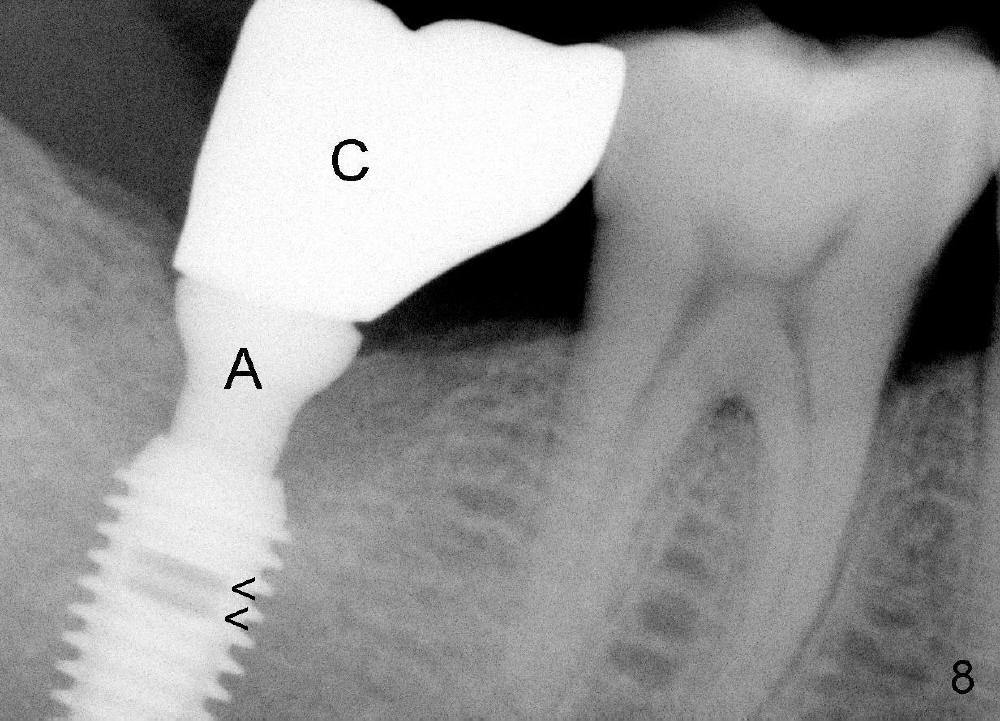

It is advantageous to place implant immediately or shortly (4-8 weeks) after extraction.  But most teeth to be extracted are potentially infected, such as in the case of Ms. Pei (Fig.1).  Periapical radiolucency (PARL) is not obvious prior to extraction. Six weeks post-extraction, osteotomy is finished with bone expansion and drilling (Fig.2 D, 5x14mm).  Tatum tapered implant is placed (Fig.3 I: 6x14). So far PARL is minimal if any (Fig.2,3 <).  Pain develops approximately 20 days post-implantation with expanding PARL (Fig.4 <).  Antibiotic treatment does not resolve the infection.  The implant has to be removed.  Infected granulation tissue is thoroughly removed from the apical portion of  the socket (Fig.5 <) with a curette (C).  Scaling and root planing is done for 4 quadrants.  A month later, potentially infected hard tissue is removed by reamers (Fig.6 D, 5 mm).  Bicon implant is buried inside the bone and separated from the oral cavity (Fig.7 I, 5x8).  At that time, there is a gap next to the implant (>).  Five months later, the gap disappears, suggesting implant osteointegration (Fig.8).  Extraoral cementation is done between abutment (A) and crown (C).  The abutment/crown unit is tapped into the implant with 2 visible threads (<).  The latter indicates that the abutment is completely seated.  Dashed lines in Fig.5-7 denote the upper border of the inferior alveolar canal.  PAs are taken 6 months (Fig.9) and 1 year 7 months (Fig.10) post cementation.  In all, it is a hassle to do re-implantation.  Efforts should be exerted to prevent post-implant infection.